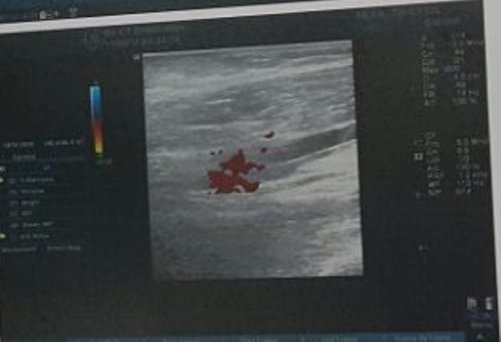

Hình ảnh siêu âm cánh tay bé trai.Hình ảnh siêu âm cánh tay bé trai.

Bác sĩ Võ Hòa Khánh, Bệnh viện Chấn thương Chỉnh hình TP HCM cho biết bé nhập viện trong tình trạng cánh tay sưng đau, đầu chi nhạt, mạch quay khó bắt, không sử dụng được các ngón tay.